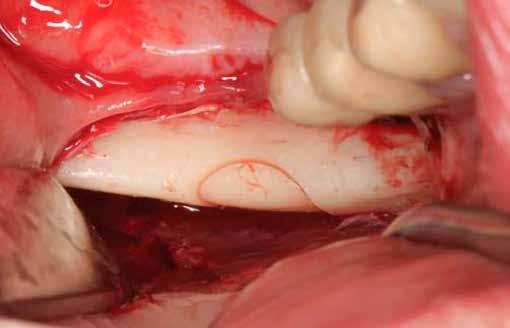

Javasolt, hogy a lehető legpontosabban ragaszkodjunk a hangár technika műtéti protokolljához. Miután a csontlemezeket oszteoszintézis csavarokkal rögzítettük, az okkluzális csontlemezt egy trepán fúróval átfúrjuk (lehetőleg az implantátum átmérőjével megegyező méretben), majd az imp-

lantátumot ezen a nyíláson keresztül helyezzük be a korábban előfúrt helyre, amelyet előtte autológ csontrészecskékkel töltünk fel.

9. ábra: A csontlemezek jellegzetes, félhold vagy sarló alakúak. Innen ered a technika elnevezése.

10. ábra: A lemezek vastagsága mindössze 2,1 mm, amely szükségtelenné teszi a további elvékonyítást.

11. ábra: Lehetőség van több lemez vételére, egymás melletti területekről.